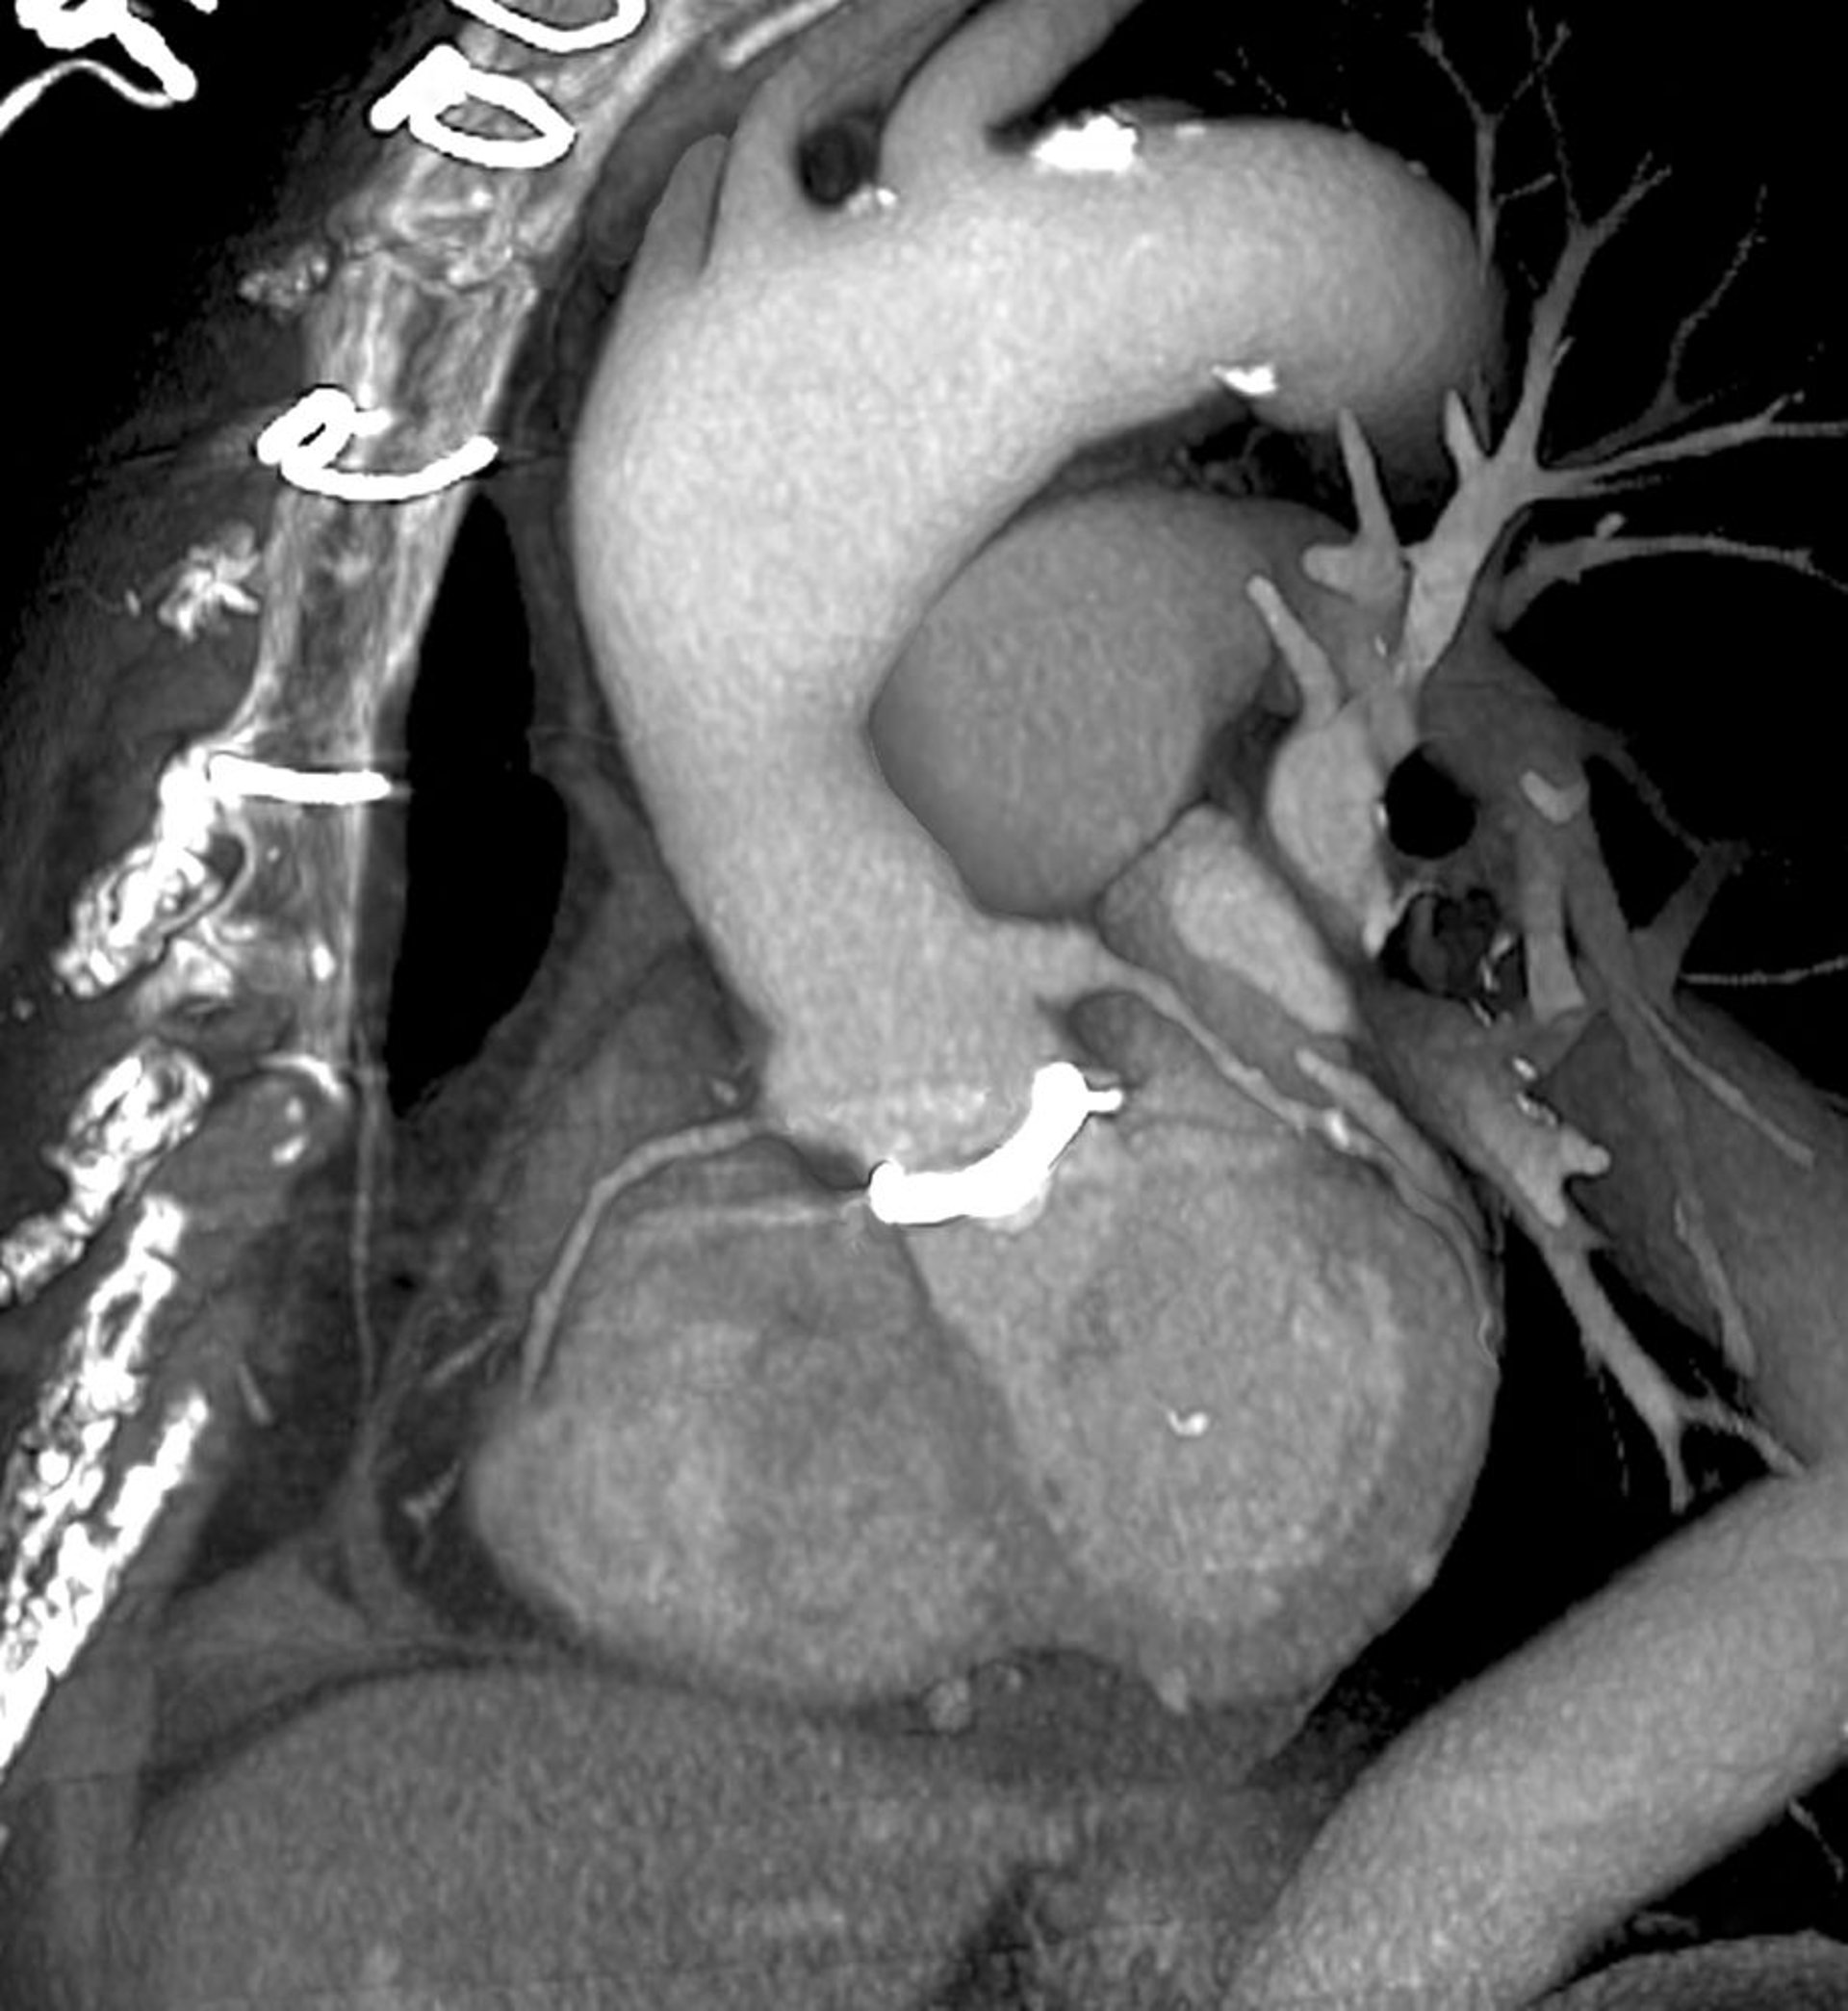

Chụp CT tim (chụp 3D van tim giả)

Đây là hình ảnh nhìn chụp nghiêng về phía bên trái, nhìn về phía trước ngực (bên trái). Van tim giả (màu trắng) có thể nhìn thấy ở trung tâm, nơi động mạch chủ (trung tâm trên) gặp tim (trung tâm dưới). Các mũi khâu được sử dụng để đóng ngực có thể nhìn thấy ở phía trên bên trái.